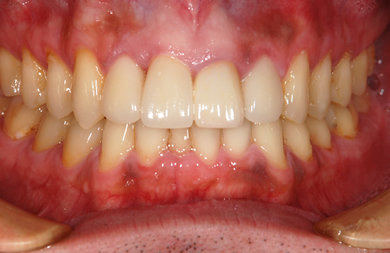

| 性別/年齢 | 男性 / 33歳 | ||||||||||||||||||||||||||||||||

| 治療方針 | 透明感のあるオールセラミックを使用して審美的・機能的回復を行う。 | ||||||||||||||||||||||||||||||||

| 治療内容 | オールセラミック6本(オールセラミック用の土台2本) | ||||||||||||||||||||||||||||||||

| 総治療費 | 741,129円 | ||||||||||||||||||||||||||||||||

| 治療期間 | 6ヶ月 |